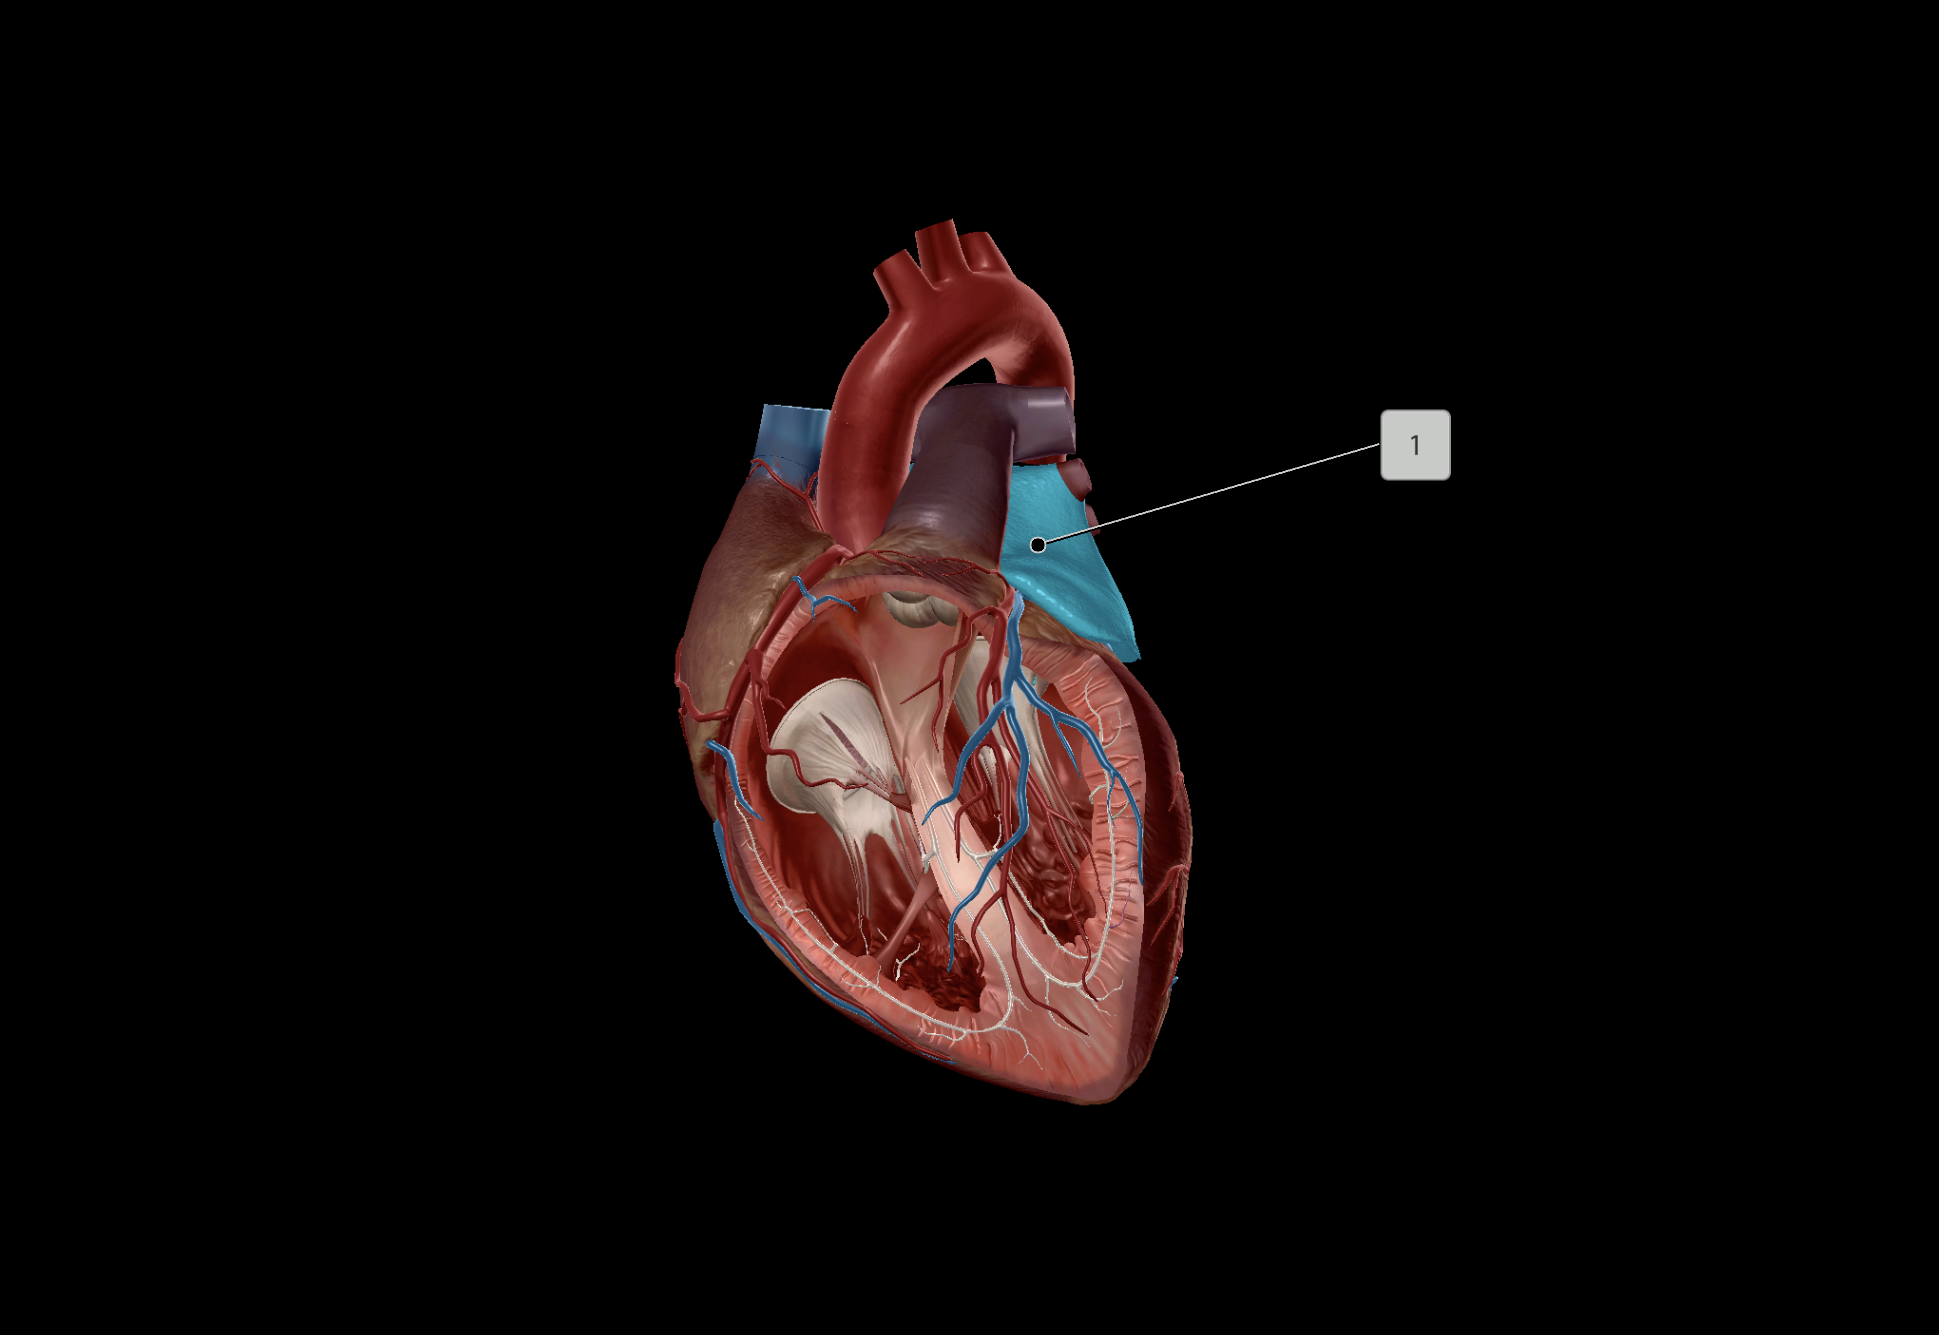

Left Atrium

Right Atrium

Left Ventricle

Right Ventricle

Tricuspid Valve

Bicuspid Valve

Aortic Valve

Papillary Muscle

Pulmonary Valve

Interventricular Septum

Chordae Tendineae

Interatrial Septum

Coronary Sulcus